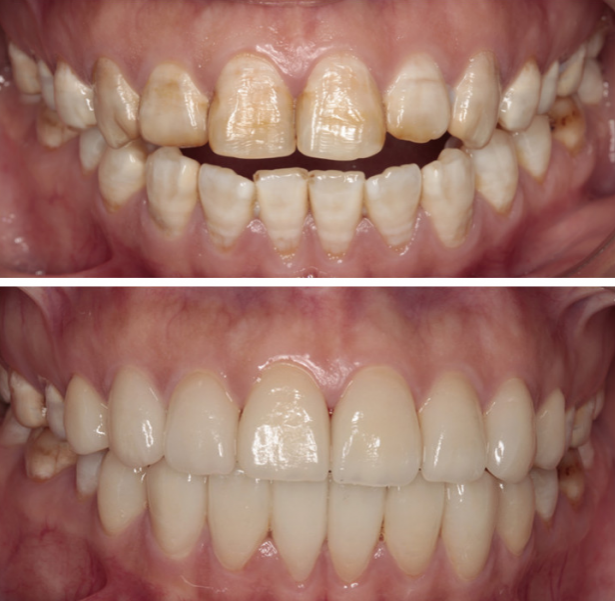

· 牙齿美白(漂白): 通过药物美白,能有效淡化氟斑牙的颜色,改善轻中度的着色。

· 树脂渗透术: 一种微创技术,用透明树脂渗入多孔釉质,有效遮挡白垩色斑,效果自然。

· 牙齿贴面: 在牙齿表面粘贴一层薄薄的瓷或树脂贴面,能完美覆盖任何颜色的斑块和轻微缺损,效果显著。